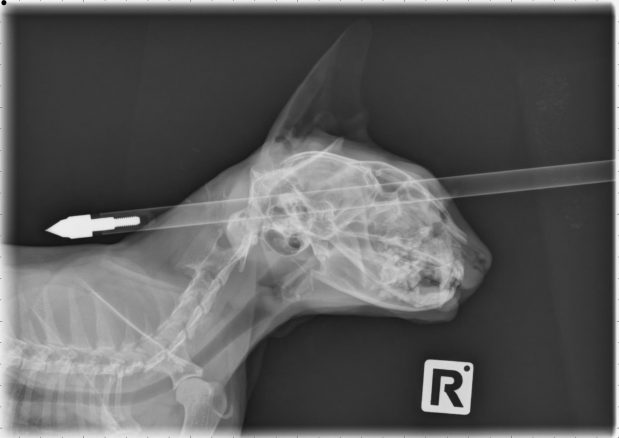

Kahdeksan elämää jäljellä – kissa sai nuolen päähänsä ja selvisi

Teini-ikäinen mies ampui omien sanojensa mukaan kissaa vahingossa nuolella päähän.

Moo Moo -niminen kissa selvisi kuin ihmeen kaupalla hengissä saatuaan nuolen päähänsä viime viikolla. 18-vuotias mies oli ollut harjoittelemassa jousiammuntaa ja yksi hänen nuolistaan osui vahingossa kissaan. Moo Moo oli koettanut päästä kotiinsa nuoli päässään, mutta ei ollut mahtunut kissanluukusta sisään. Muutaman vuoden ikäisen kissan omistaja kiidätti lemmikkinsä eläinlääkäriin, missä nuoli poistettiin. Kissaa hoitanut eläinlääkäri Jonathan Bray järkyttyi nähtyään Moo Moon ensimmäisen kerran, mutta oli iloinen huomattuaan kuinka vähän vaurioita nuoli oli tehnyt. ”Kissalla oli hieman ammoja nenässä ja silmäkuopassa, mutta se on erittäin onnekas kissa. Nuolen vauhti on varmasti säikäyttänyt kissan, joten se on todella rohkea. Maanantaiaamuna kissa voi hyvin, se oli iloinen ja haava paranee eikä nuolesta aiheutunut mitään pitkäaikaista haittaa”, Bray kertoo.